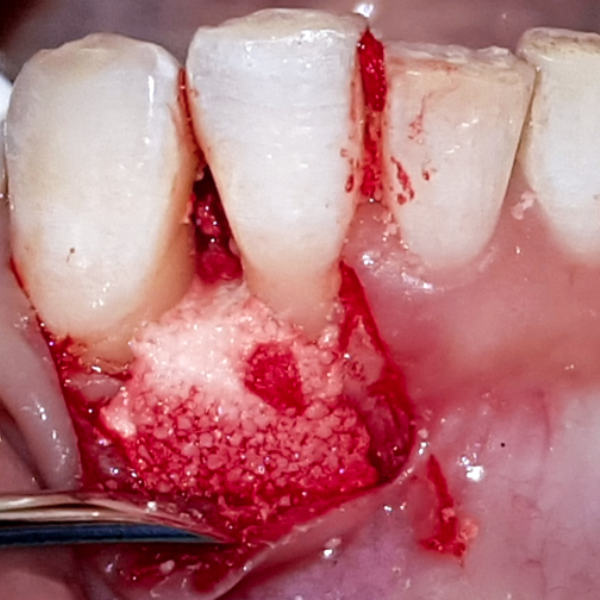

Immediate Dental Implant Placement

Tooth 14 slightly increased mobility, tenderness and bite pain. Suspected root fracture